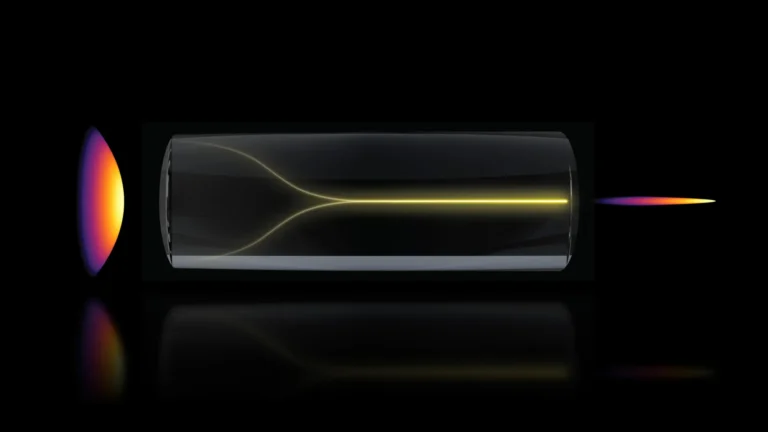

To meticulously untangle the complex interplay of factors and establish a definitive causal link, the researchers employed a sophisticated methodological approach known as Mendelian randomization. This technique serves as a powerful proxy for randomized controlled trials, leveraging naturally occurring genetic variations that influence specific traits, in this instance, BMI. By examining common genetic variants predisposed to higher BMI, the researchers effectively simulated the impact of interventions aimed at altering body weight, analogous to administering a weight-loss medication. In the realm of clinical trials, participants are typically assigned randomly to receive either an active therapeutic agent or a placebo, thereby isolating the effect of the treatment. Similarly, Mendelian randomization capitalizes on the random inheritance of genetic material from parents to offspring. Certain genetic predispositions are randomly passed down, leading to variations in BMI among individuals, independent of other lifestyle or environmental factors that might otherwise confound research outcomes. This inherent randomness in genetic inheritance allows scientists to observe the impact of BMI on disease development with a remarkable degree of clarity, minimizing the influence of confounding variables that can often obscure true cause-and-effect relationships in observational studies. Through this rigorous genetic lens, the research team was able to confidently identify high BMI as a direct contributor to an elevated risk of developing dementia.